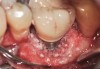

Problem: The implant is placed too facially, and there is significant labial gingival recession, contour change, and mucosal discoloration around the implant, abutment, and crown (Figure 3 and Figure 4). The implant attachment apparatus is intact and healthy, but the patient has a thin periodontal phenotype.

Solution: (1) Decoronate the implant with a sterile cover screw. (2) Place a tooth-supported fixed transitional provisional restoration such as a temporary resin-bonded–retained “Maryland-type” bridge and allow the mucosal tissues to “creep” over the cover screw for a few weeks. (3) Place a subepithelial connective tissue graft to augment the soft tissues both horizontally and vertically. (4) Two months later, perform a second-stage implant uncovering and place a flat-profiled healing abutment. (5) After a few weeks of soft-tissue healing, manage the subgingival restorative contours of the provisional and definitive restoration.

The following case report provides an example of this case scenario: A 28-year-old white female patient presented with her maxillary right lateral incisor significantly longer than the contralateral tooth following restoration of an existing crown that was 10 years old (Figure 3). The patient was dissatisfied with the esthetic appearance of the restoration due to the increased length, recession of the gingival tissues, and discoloration of the surrounding mucosa (Figure 4). Similar to case scenario No. 1, the first step in treatment was to decoronate the healthy implant by placing a flat surgical cover screw and employing a provisional resin-bonded-retained (RBR) prosthesis as a transitional fixed restoration (Figure 5 and Figure 6). The gingival augmentation in situ was allowed to take place for 2 to 3 weeks and was evaluated after that time (Figure 7).

Fig 3. A patient presented with a high smile line and midfacial recession of the maxillary right lateral incisor as evidenced by the increased tooth length compared with the contralateral lateral incisor.

Fig 4. Intraoral view of tooth No. 7 with the gingival zenith more apical than the adjacent central incisor and canine tooth.